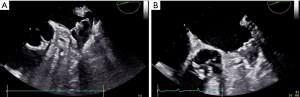

A total of 57 AF patients underwent successful Watchman device implantation and received either rivaroxaban or warfarin post-LAAO at our institution. Of which, 10 patients receiving rivaroxaban in the periprocedural period were included. Baseline characteristics of the study patients are outlined in Table 1. These cases had high risks of stroke and bleeding, with the median CHA2DS2-VASC score of 5 and HAS-BLED score of 4. The most common risk factors for stroke were hypertension (9 patients) and a history of ischemic stroke (5 patients). Permanent AF was present in 8 patients. All the patients completed a planned 45-day regimen of rivaroxaban, and no DRT, peri-device leakage, thromboembolic complications, and major bleeding were observed at time of follow-up (6 weeks, 6 months, and 12 months) (Table 1, Figure 1). One patient experienced a minor epistaxis and another had a gingival bleeding and ecchymosis on left arm during the 6 weeks follow-up, and without rivaroxaban discontinuation. Therefore, insights from the above finding, rivaroxaban seemed to be a suitable antithrombotic agent after the Watchman device implantation.